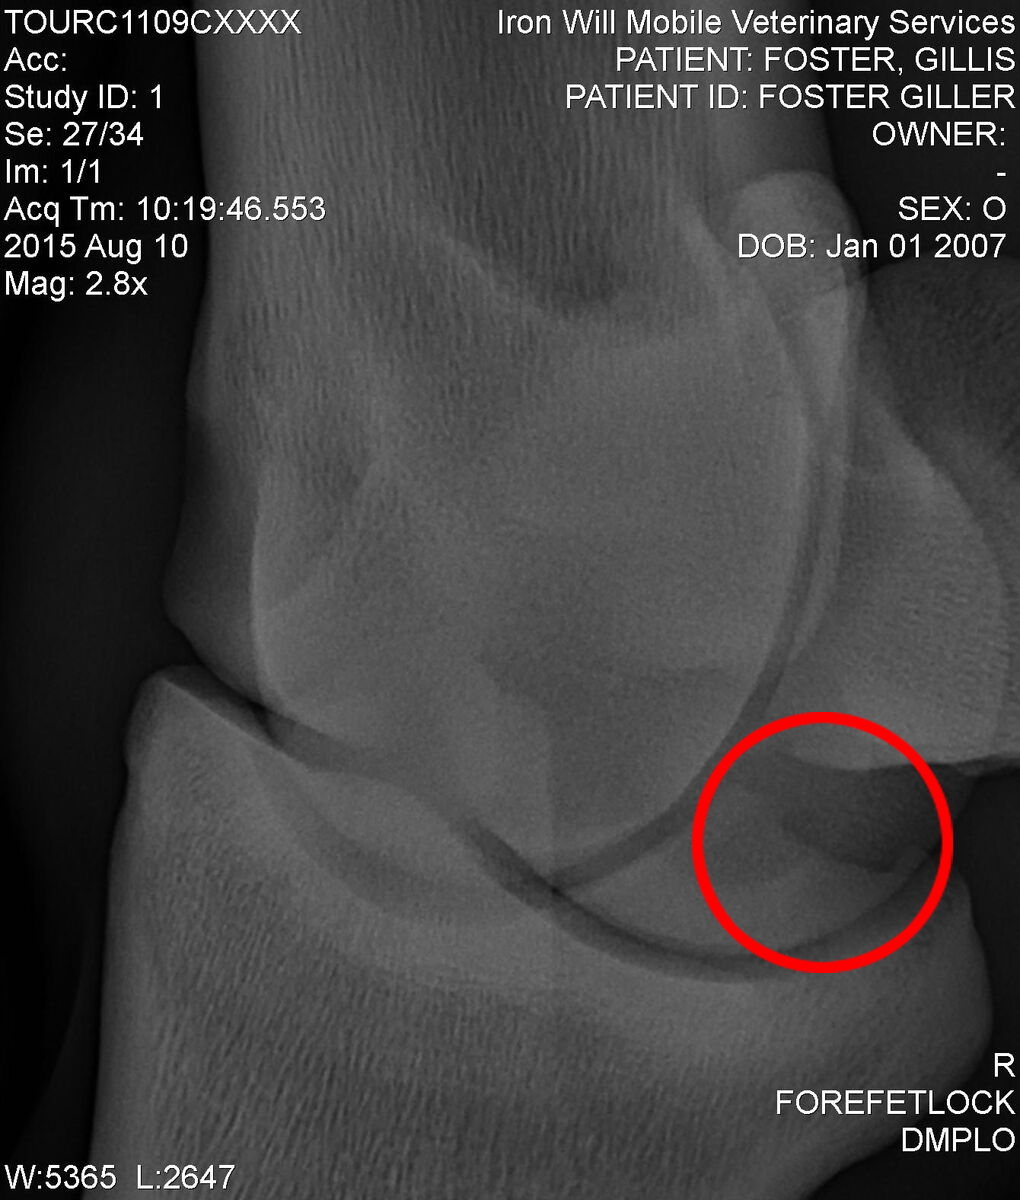

The second chip is a bit tricker to spot. It’s back by the sesamoid bones, and here we are looking through the fetlock at a diagonal angle. For a better view of what the chip looks like, here is the other side of the fetlock compared to the bone chip.